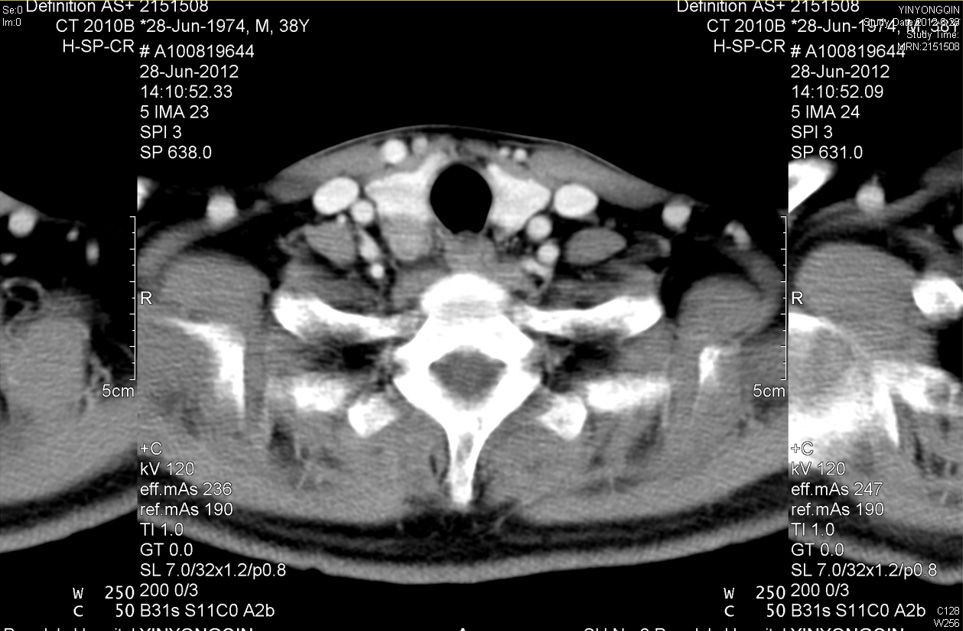

原发性甲状旁腺功能亢进的精准诊断包括定性和定位诊断。最简单方便而快捷、也是比较典型的验血指标是血钙和甲状旁腺激素,一般都增高,三级或两级甚至基层医院均可化验;其他生化改变还包括碱性磷酸酶、尿钙、尿磷高而血磷低。有时为了鉴别诊断以及发现无症状、血钙或PTH正常的早期甲旁亢,还需参考白蛋白、1,25-二羟维生素D、肾功能、24小时尿钙等指标来协助诊断,甚至采用高钙抑制试验来明确诊断。而精准定位诊断主要根据颈部专家超声和/或甲状旁腺显像(MIBI/CT融合显像)(图2),必要时采用颈部增强CT(图3)、全身骨扫描。MIBI和CT检查对诊断有无异位在胸骨后或上纵隔内的甲状旁腺非常重要。

图3 右侧甲状旁腺癌 增强CT